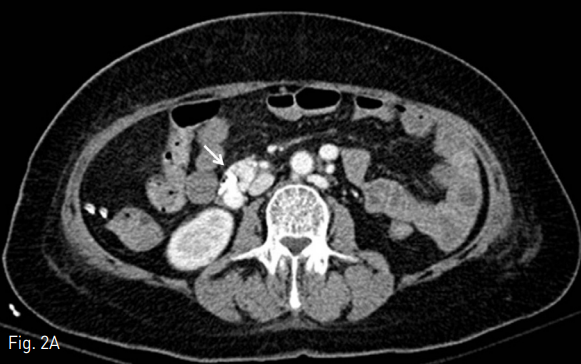

색전술 직후에 시행한 추적 전산화 단층촬영에서 십이지장 정맥류가 방사선비투과성 Lipiodol로 완전 충전된 것을 확인함 (Fig. 3D).

D. The duodenal varix is completely filled with radiopaque lipiodol (open arrowhead) on follow-up CT scan.